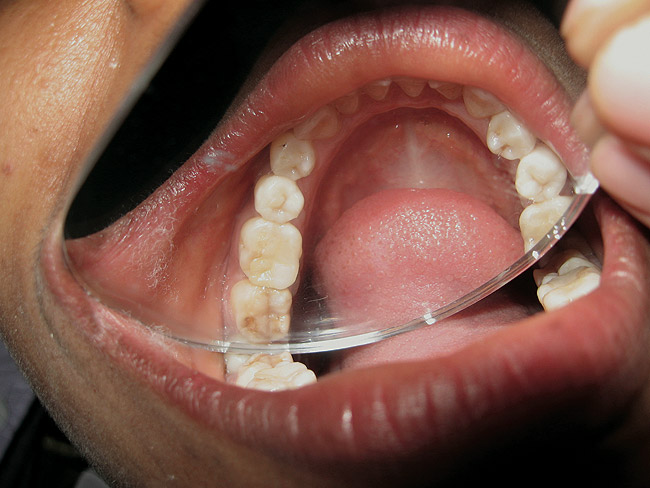

Figure 9  RBC inlay

Figure 9

Figure 10  RBC inlay

Figure 10

The search for an ideal direct esthetic restorative material is still ongoing. Among the array of RBC materials, some are readily available in the market (flowable, packable, and fiber-reinforced), others have just recently been introduced (siloranes-based), and a few are still in development phase (fluoride-releasing). Individual properties of different RBC materials define their advantages, disadvantages, and clinical uses. Each type of RBC material has its own virtues in some clinical aspects and shortcomings in other aspects. Every material possesses either one or the other ideal properties of a restorative material, but not all of them. Therefore, it is important for a clinician to use every material judiciously and for a clinical application for which it is best suited (Figure 5, Figure 6, Figure 7, Figure 8, Figure 9 and Figure 10).